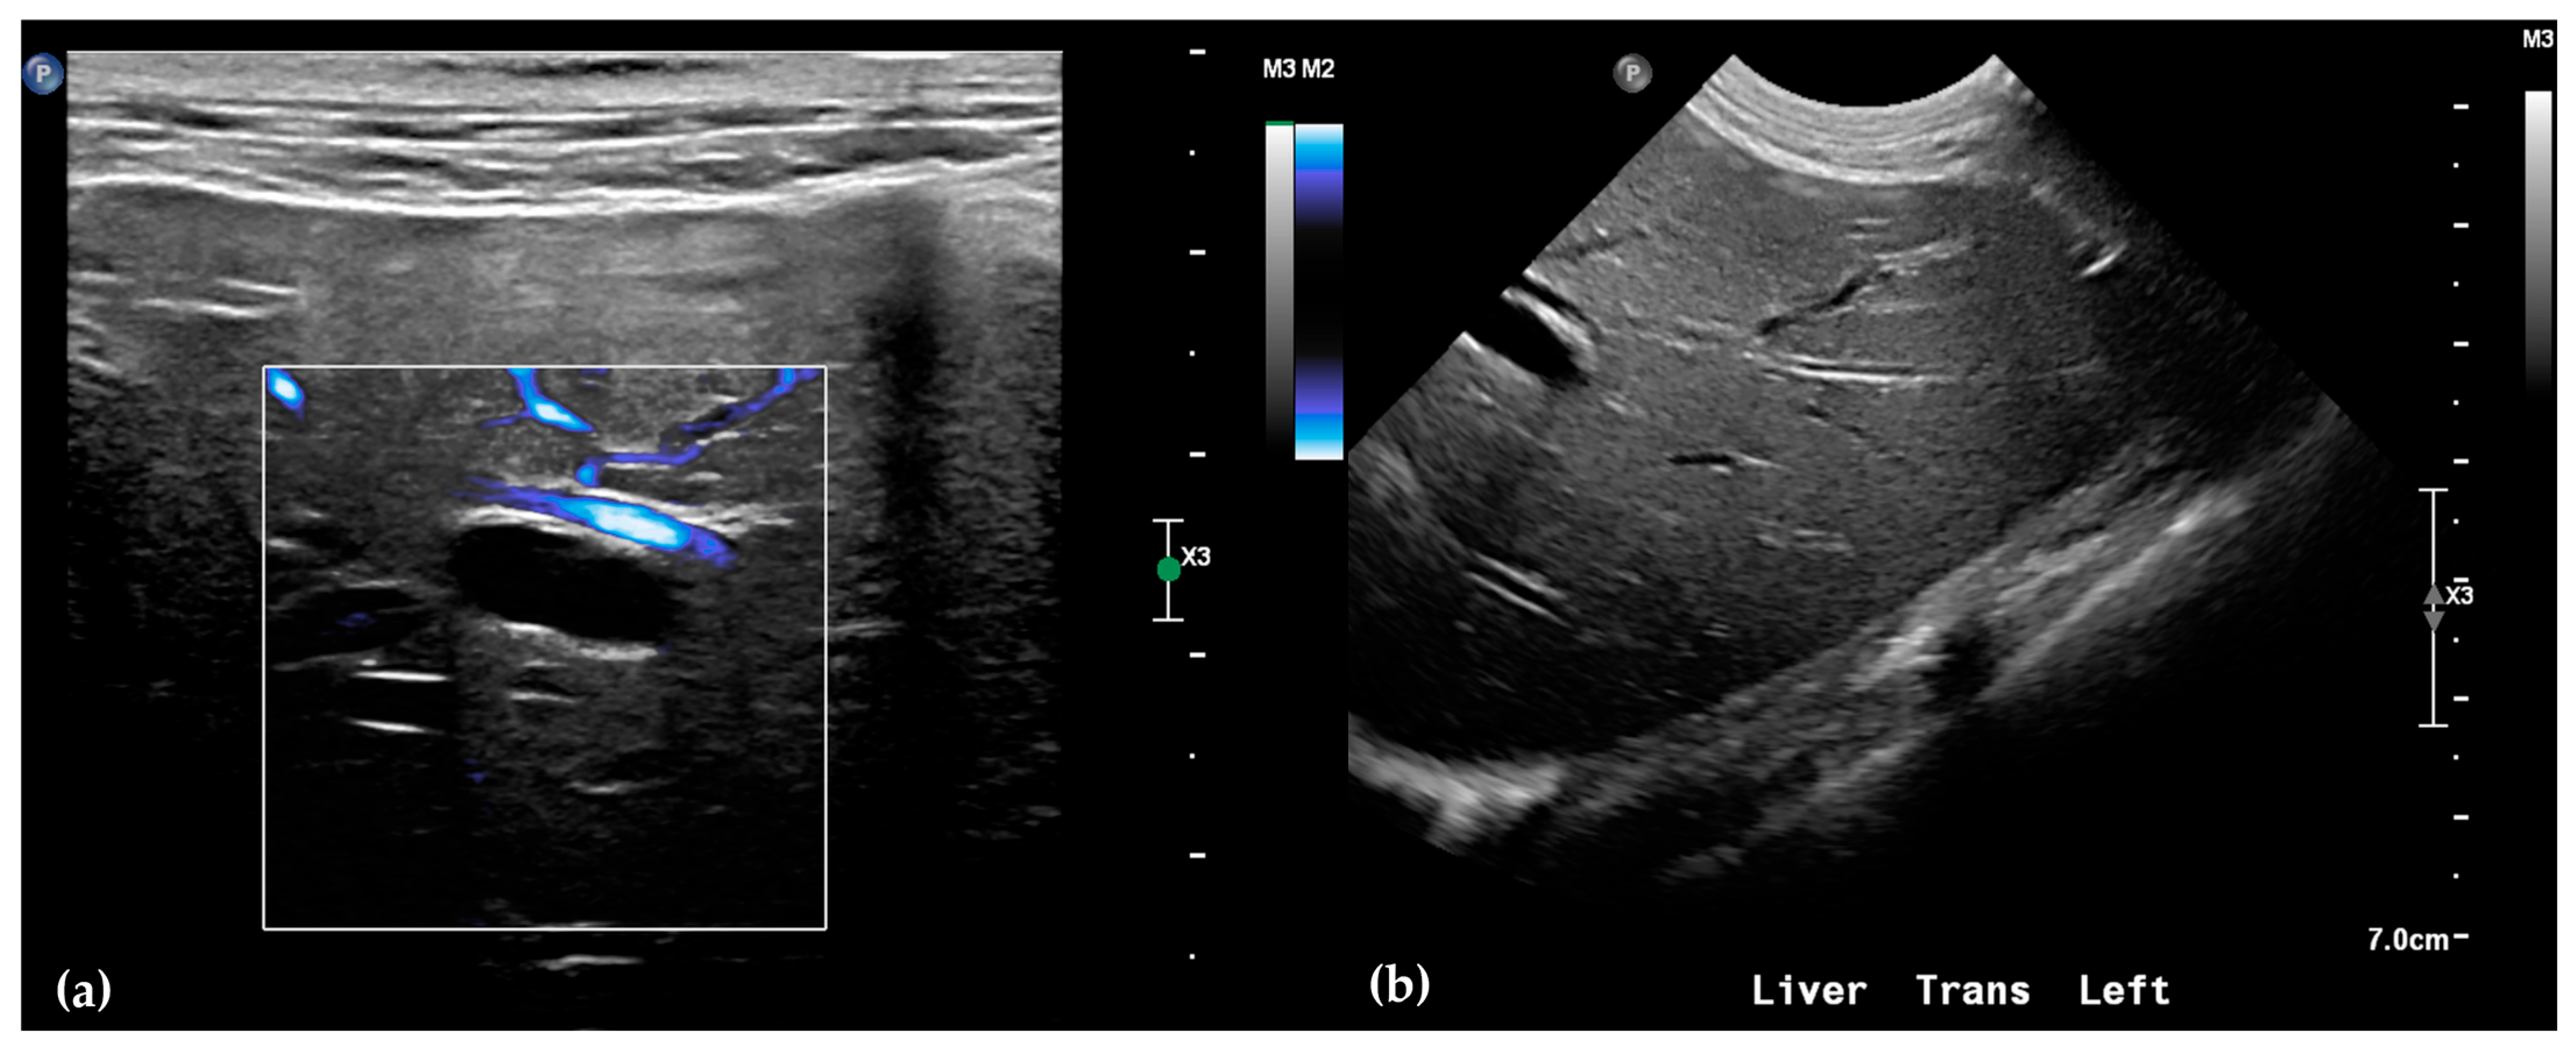

Abdominal radiographs showed no significant abnormalities except a large amount of fecal material in the large intestine. The patient was placed in dorsal recumbency for an abdominal ultrasound (microconvex and linear probes 12–18 MHz, Epiq 5G, Philips Ultrasound, Bothell, WA, USA), with the ventrum shaved from above the xiphoid to the pubis in a roughly square-shaped region. Ultrasound coupling gel and alcohol were used for image optimization. The gallbladder was moderately filled with anechoic fluid and the cystic duct appropriately tapered to the common bile duct (CBD). The CBD could not be traced in its entirety, but the more distal identified segments were multifocally dilated, measuring up to 0.6 cm in diameter (outer wall to outer wall; Figure 1a). At its distal-most aspect, as it approached the duodenal papilla, the CBD abruptly tapered without a discrete intraluminal or extraluminal cause (Figure 1b). Several intrahepatic biliary ducts within the left liver hemisphere were distended distally, measuring up to 0.5 cm in dilation (inner wall to inner wall; Figure 2a,b). No intrahepatic biliary duct dilation of the right hepatic hemisphere was noted. Due to a concern for an unidentified biliary duct obstruction contributing to the patient’s clinical signs/changes, a dual phase contrast abdominal computed tomographic (CT) study was pursued for further evaluation.

Figure 2.

Ultrasound of the left liver. Power Doppler, within white box, of the left liver demonstrating slow flow (blue) through adjacent hepatic vasculature and no flow (black) within the anechoic structure, consistent with a dilated intrahepatic biliary duct (a). Several anechoic tubular structures without peripheral hyperechoic walls, consistent with peripheral intrahepatic biliary duct dilation (b).